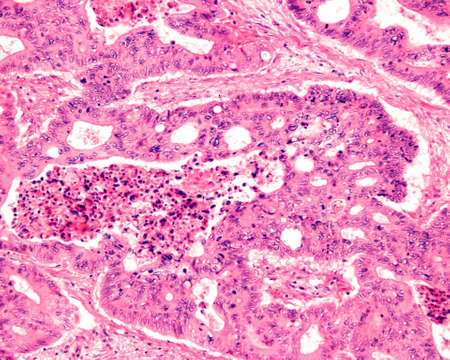

Breast cancer of the woman diseased tissue 100x